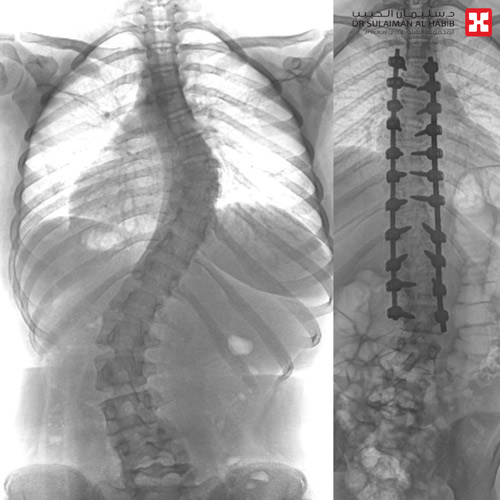

وأظهرت الفحوصات إصابتها بحالة انحراف «جنف صدري» بدرجة «47» للفقرات الصدرية وقطني بدرجة «50»، ودرس الفريق الطبي الحالة، وخلص إلى ضرورة التدخل الجراحي لعلاج العيوب، والحد من المضاعفات. وقد أجريت للفتاة عملية جراحية، تم فيها تقويم العمود الفقري وتثبيت ودمج الفقرات، باستخدام «22» من البراغي والقضبان المعدنية، والطعوم العظمية الصناعية، واستمرت العملية «6» ساعات متصلة.